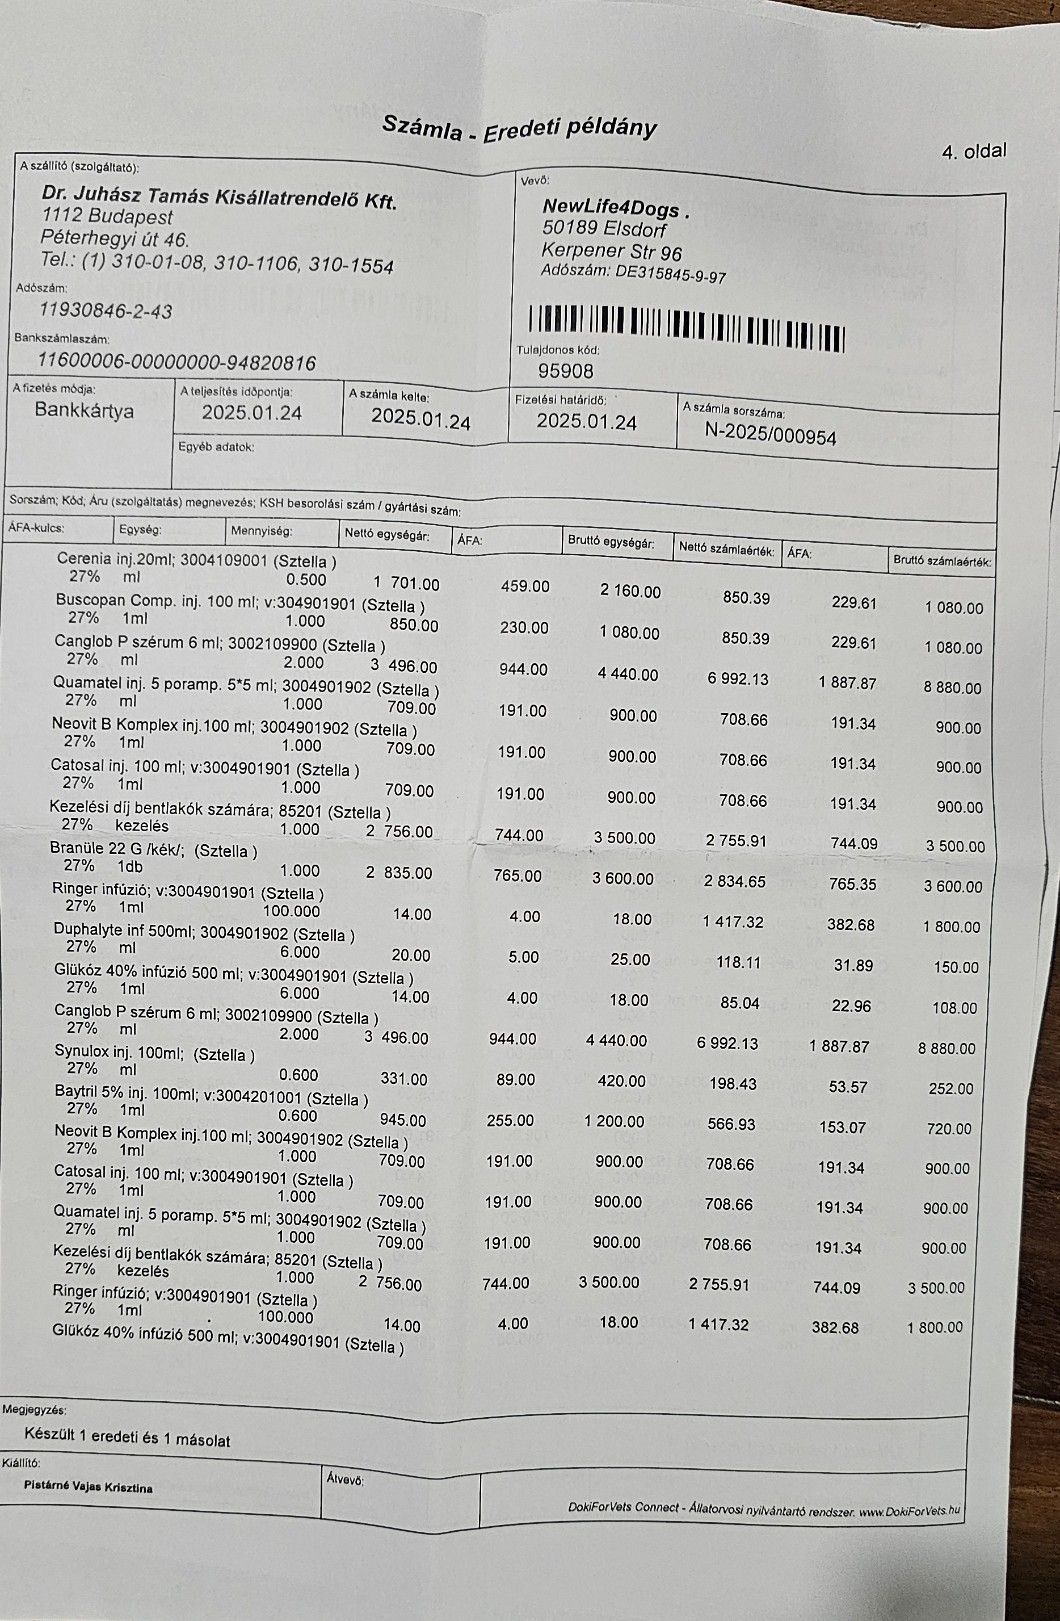

So zum Beispiel unsere kleine Stella, ein Welpen Mädchen das hier im Wald aufgefunden wurde. Nur 4 Tage nach Ankunft ging es Stella extrem schlecht und wir brachten sie in die Tierklinik zur stationären Aufnahme. Dort wurde sie intensivst medizinisch behandelt und musste 9 Tage in der Klinik verbleiben. Nur dieser eine Klinikaufenthalt verursachte Kosten in Höhe von 261.000,00 Forint ( ca. 640,00 Euro). Medikamente für die weitere Versorgung unserer Hunde musste bestellt werden. Ebenso Welpenfutter mussten wir nachkaufen. In den ersten Wochen wurden einige Hunde vergesellschaftet, damit die Quarantänestation wieder freie Zwinger hat. Denn in der Tötung warten Hunde darauf von uns abgeholt zu werden. Dies wird nun in den nächsten Tagen geschehen. Auch Klinikbesuche Kastrationen wurden wieder durchgeführt. Alleine hierfür betrug der finanzielle Aufwand ca. 750.000,00 (= ca. 1840,00 Euro) in der ersten Hälfte des Monats. Leider ist zur Zeit die Zeit extrem knapp, weswegen wir uns für die verspäteten Berichte entschuldigen. Doch die Rettungsaktionen und das Wohl unserer Schützlinge haben nun einmal Vorrang.

Nachdem die kleine Stella nach mehr als einer Woche die Klinik verlassen durfte, Mussten erneut einige unserer Neuzugänge dringende Not-OP´s und stationäre Aufnahme +ber sich ergehen lassen. So auch der kleine Sidney, den wir schwer verletzt mit gebrochenem Hinterbeinchen auf der Strasse in Nordungarn fanden. Sofortige Untersuchungen, Rüntgenaufnahmen und unverz+gliche Notoperation war erforderlich. Die Operation hat der kleine Mann gut überstanden. Nun benütigt er weitere Medikamente und Vitaminprodukte, damit er einen guten Heilungsprozess durchlaufen kann. Ebenso benütigt er 6 Wochen Zwingerruhe und Physiotherapie.

Auch unser lieber Oskar musste heute notfallmäßig in die Tierklinik. Aus derzeit noch unerklärlichen Gründen kann oskar sich nicht mehr auf seinen Hinterbeinen halten. Natürlich brachten wir ihn sofort in die Klinik. dort wurde er stationär aufgenommen. Nun ist eine MR untersuchung erforderlich, um die Ursache f+r die plützlichen Lähmungserscheinungen zu finden. Auch in der zweiten hälfte des Monats mussten wir wieder hohe Klinikkosten und Tierarztkosten bewältigen. Wir wären extrem erleichtert und dankbar wenn uns der ein oder andere hierbei unterst#tzen würde.